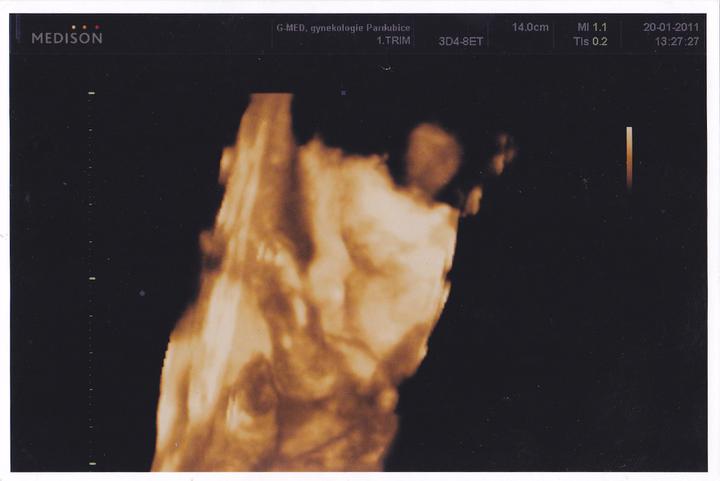

Dnes UTZ 6+1 bublinka 12mm a prcek v ní má srdíčko 🙂 nejkrásnější pocit na světě